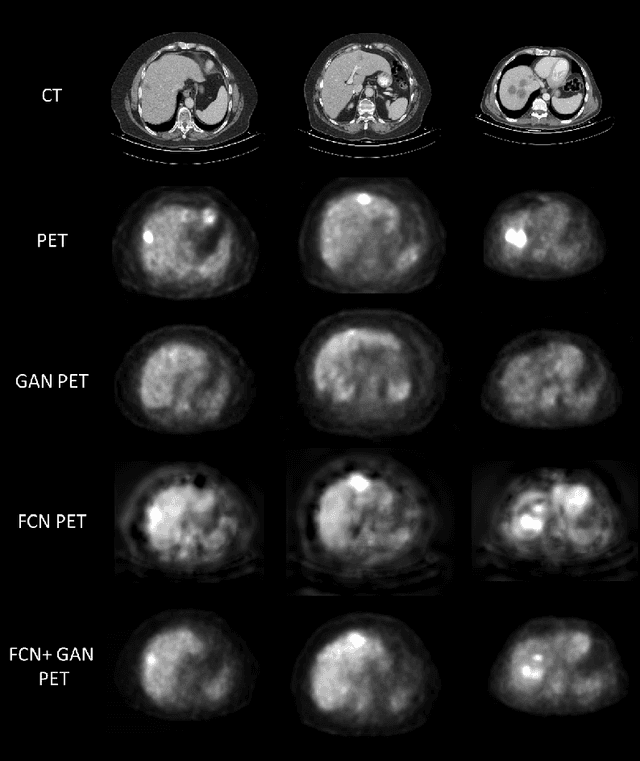

In this work we present a novel system for PET estimation using CT scans. We explore the use of fully convolutional networks (FCN) and conditional generative adversarial networks (GAN) to export PET data from CT data. Our dataset includes 25 pairs of PET and CT scans where 17 were used for training and 8 for testing. The system was tested for detection of malignant tumors in the liver region. Initial results look promising showing high detection performance with a TPR of 92.3% and FPR of 0.25 per case. Future work entails expansion of the current system to the entire body using a much larger dataset. Such a system can be used for tumor detection and drug treatment evaluation in a CT-only environment instead of the expansive and radioactive PET-CT scan.